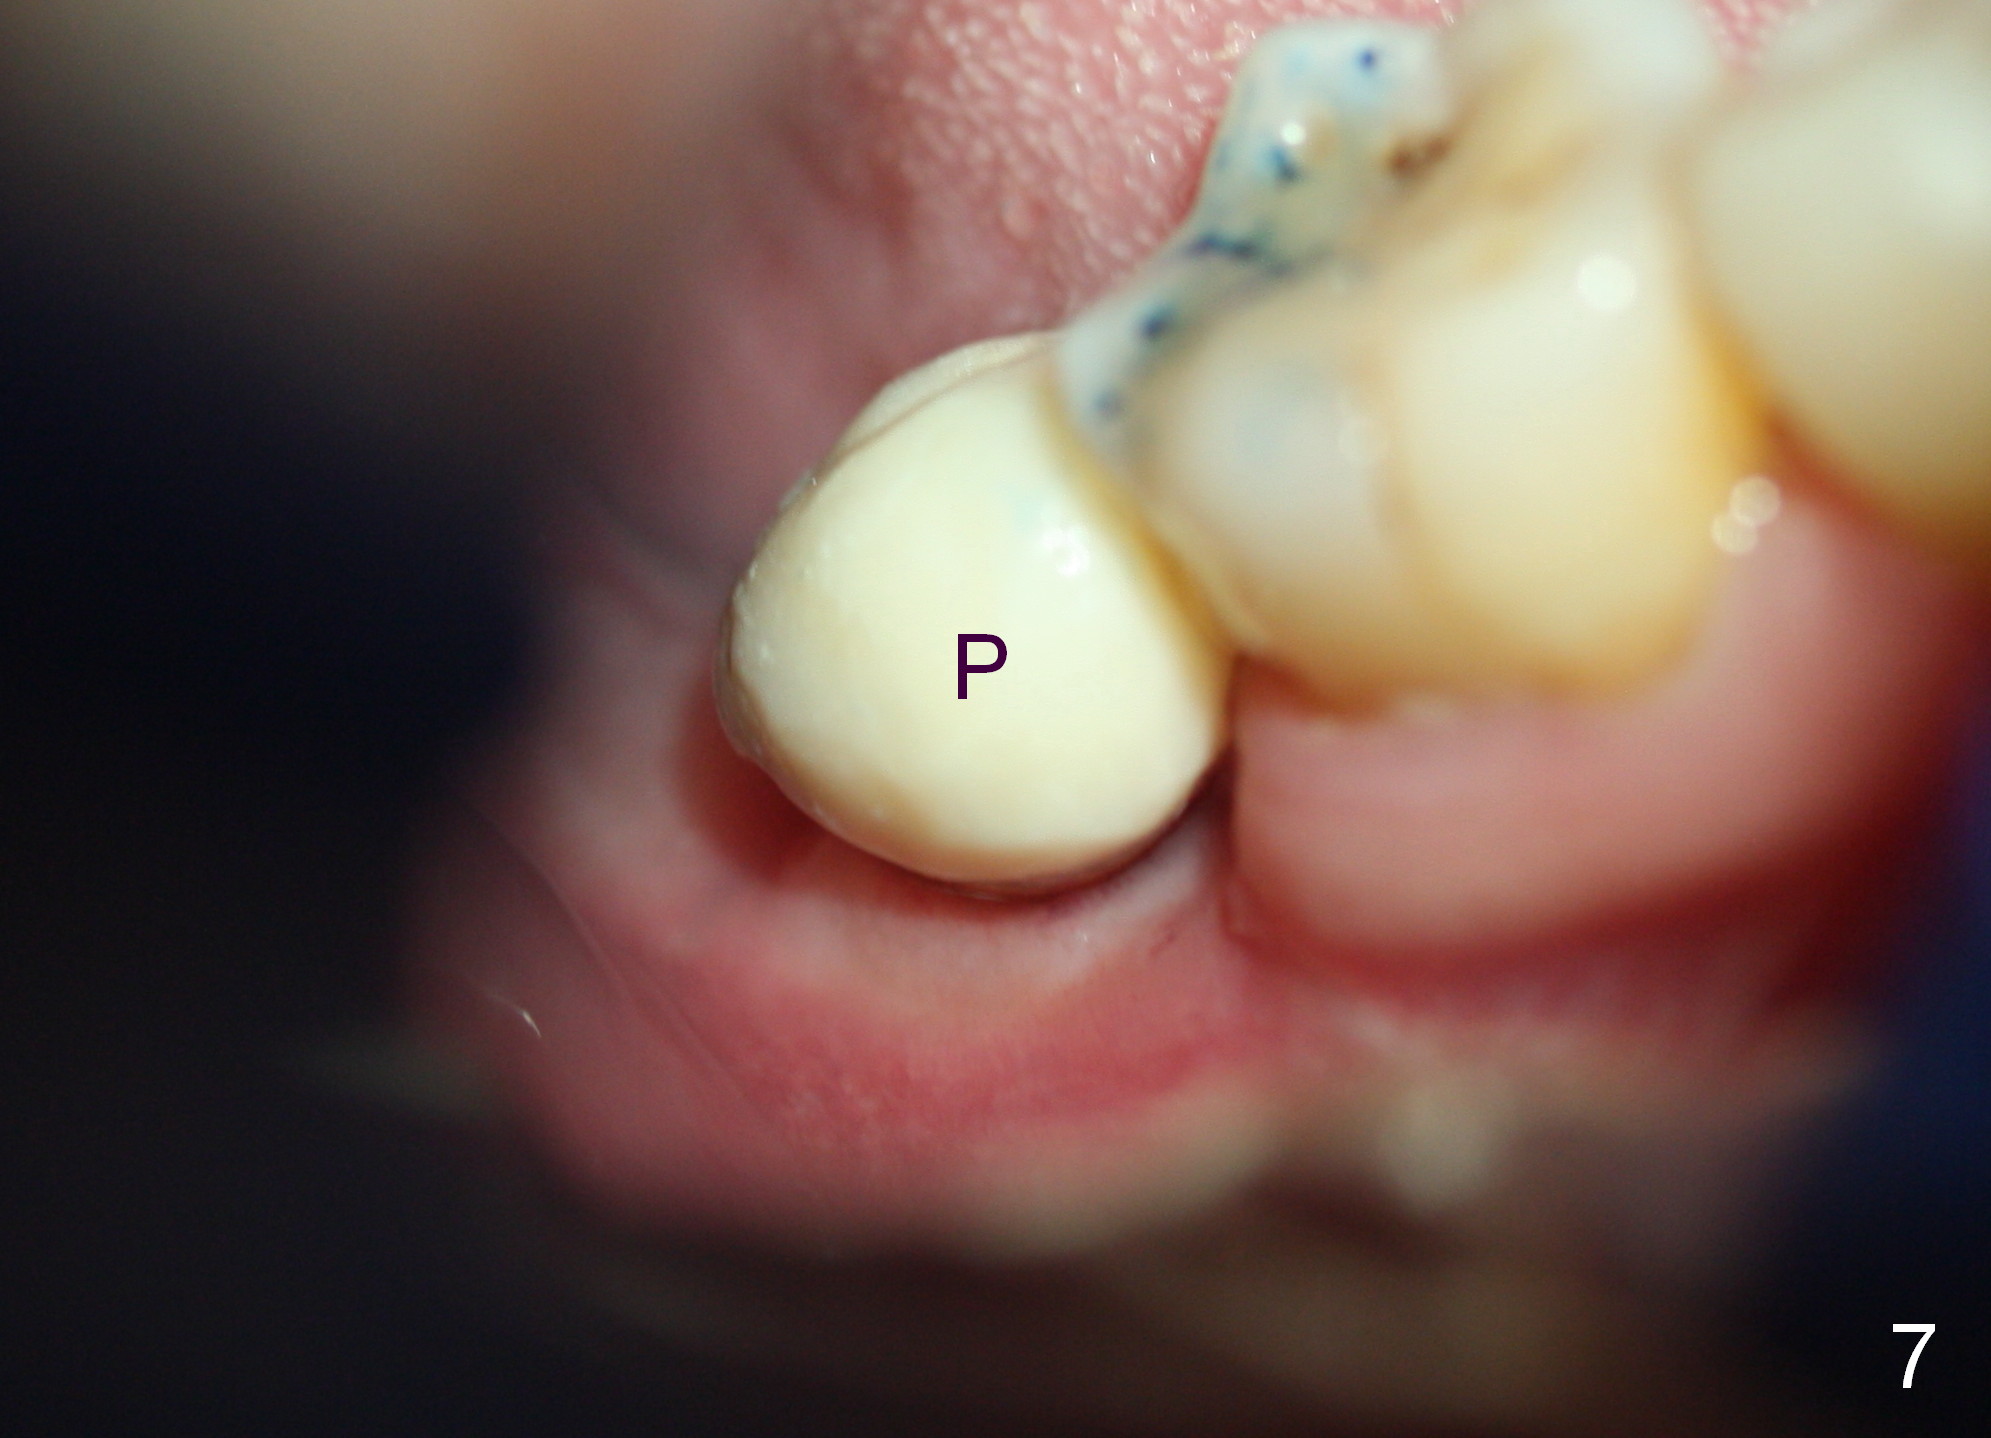

The gingiva heals around the provisional 20 days postop when the patient returns for provisional reline and recementation (Fig.7 P). Note that the margin of the provisional is lower than that of the neighboring teeth, indicating bone loss due to delayed implant placement.